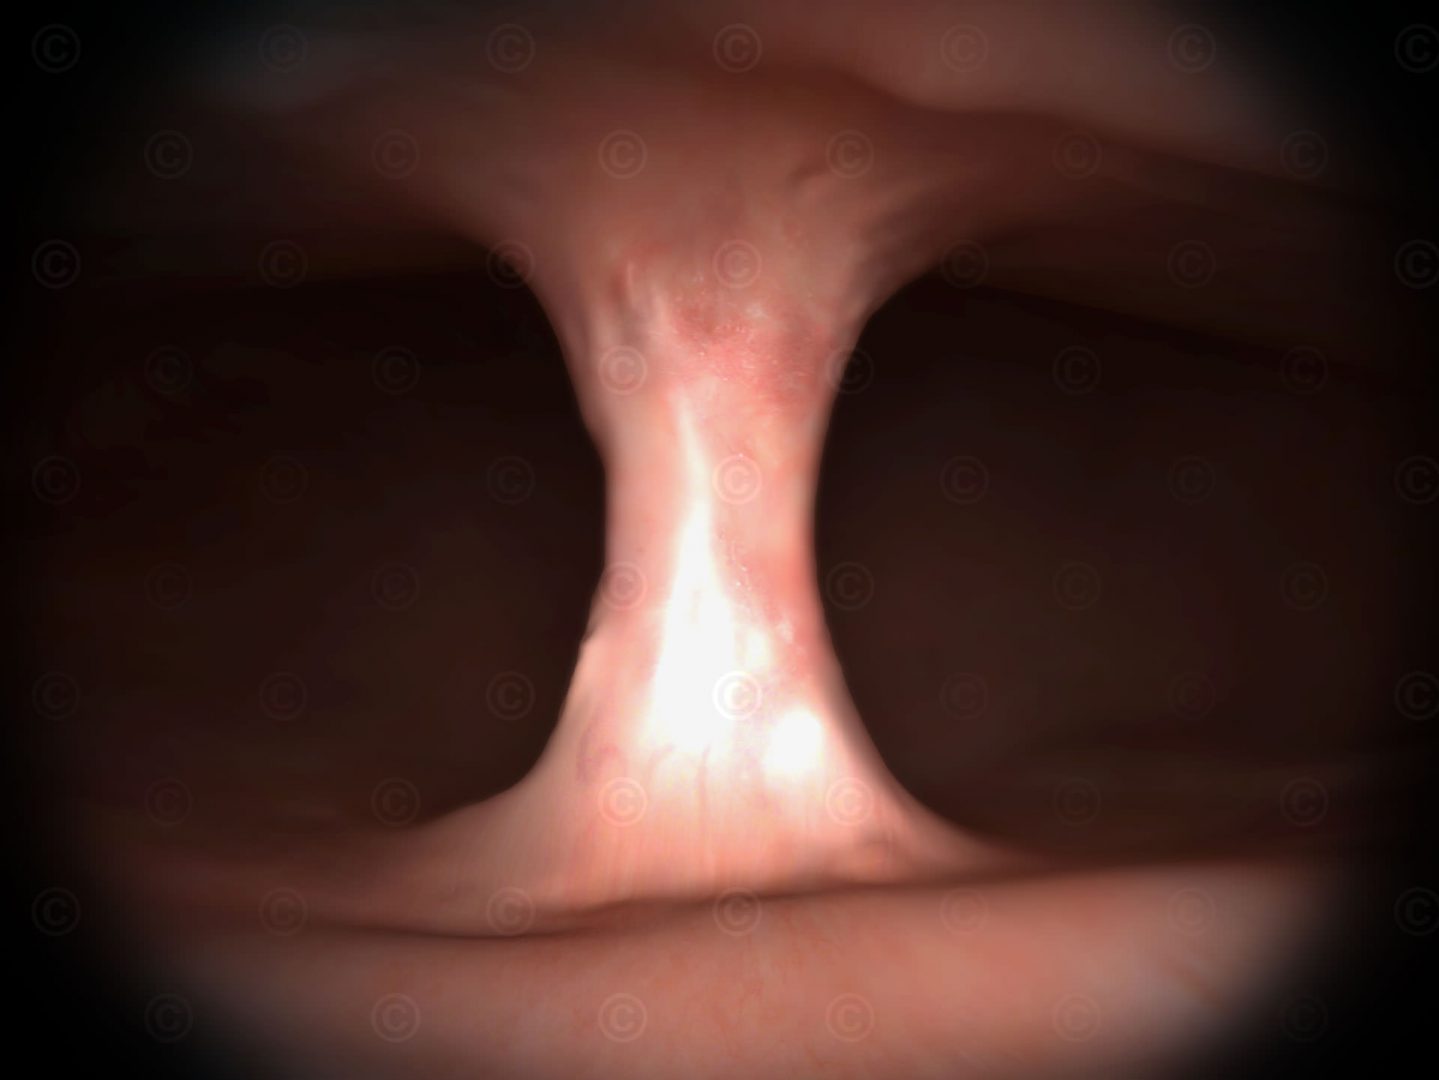

Illustration Septum in Gebärmutter

Illustration eines Septums in einer Gebärmutter.